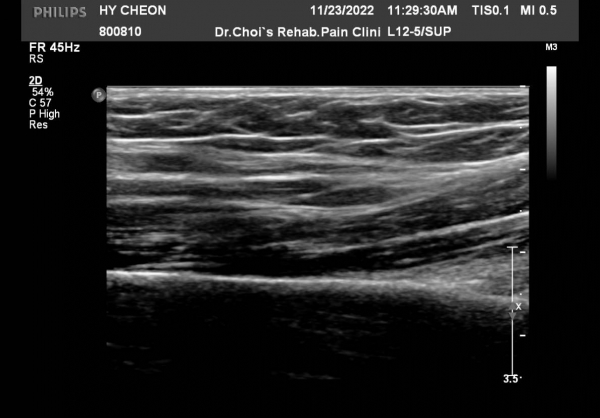

Á¤Á߽Űæ Á¾´Ü¸é °Ë»ç¿¡¼­µµ  Á¤Áß ½Å°æ ÀϺΠ´Ù¹ßÀÇ ¹æÃßÇü Àú¿¡Ä¿ ºÎÁ¾ÀÌ °üÂûµÈ´Ù(»çÁø 6, 7).